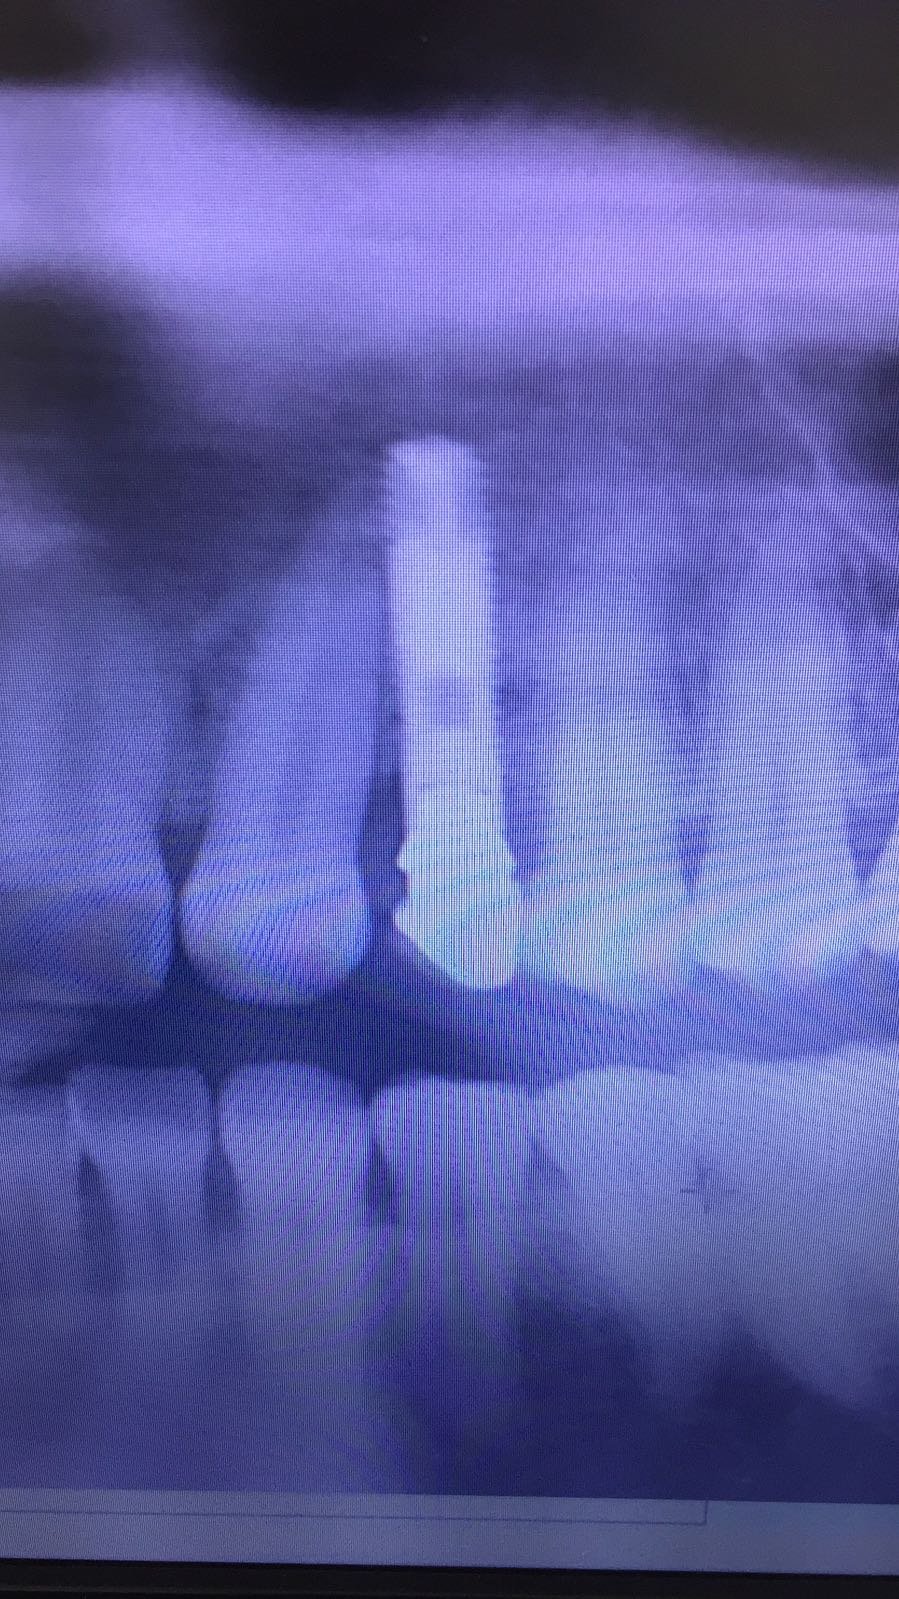

Buenos días compañeros, os adjunto este implante que me ha llegado a la clínica, seríais tan amables de decirme que implante es?, no he podido hacerle una periapical porque tengo [...]